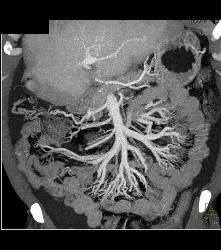

Small Bowel Extends Into Hernia Into Scrotum